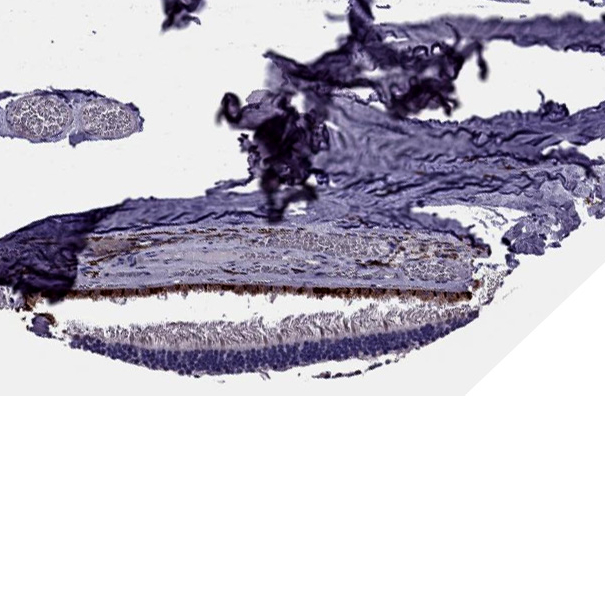

Immunohistochemical staining of human Retina shows strong membranous positivity in retinal pigment epithelium.